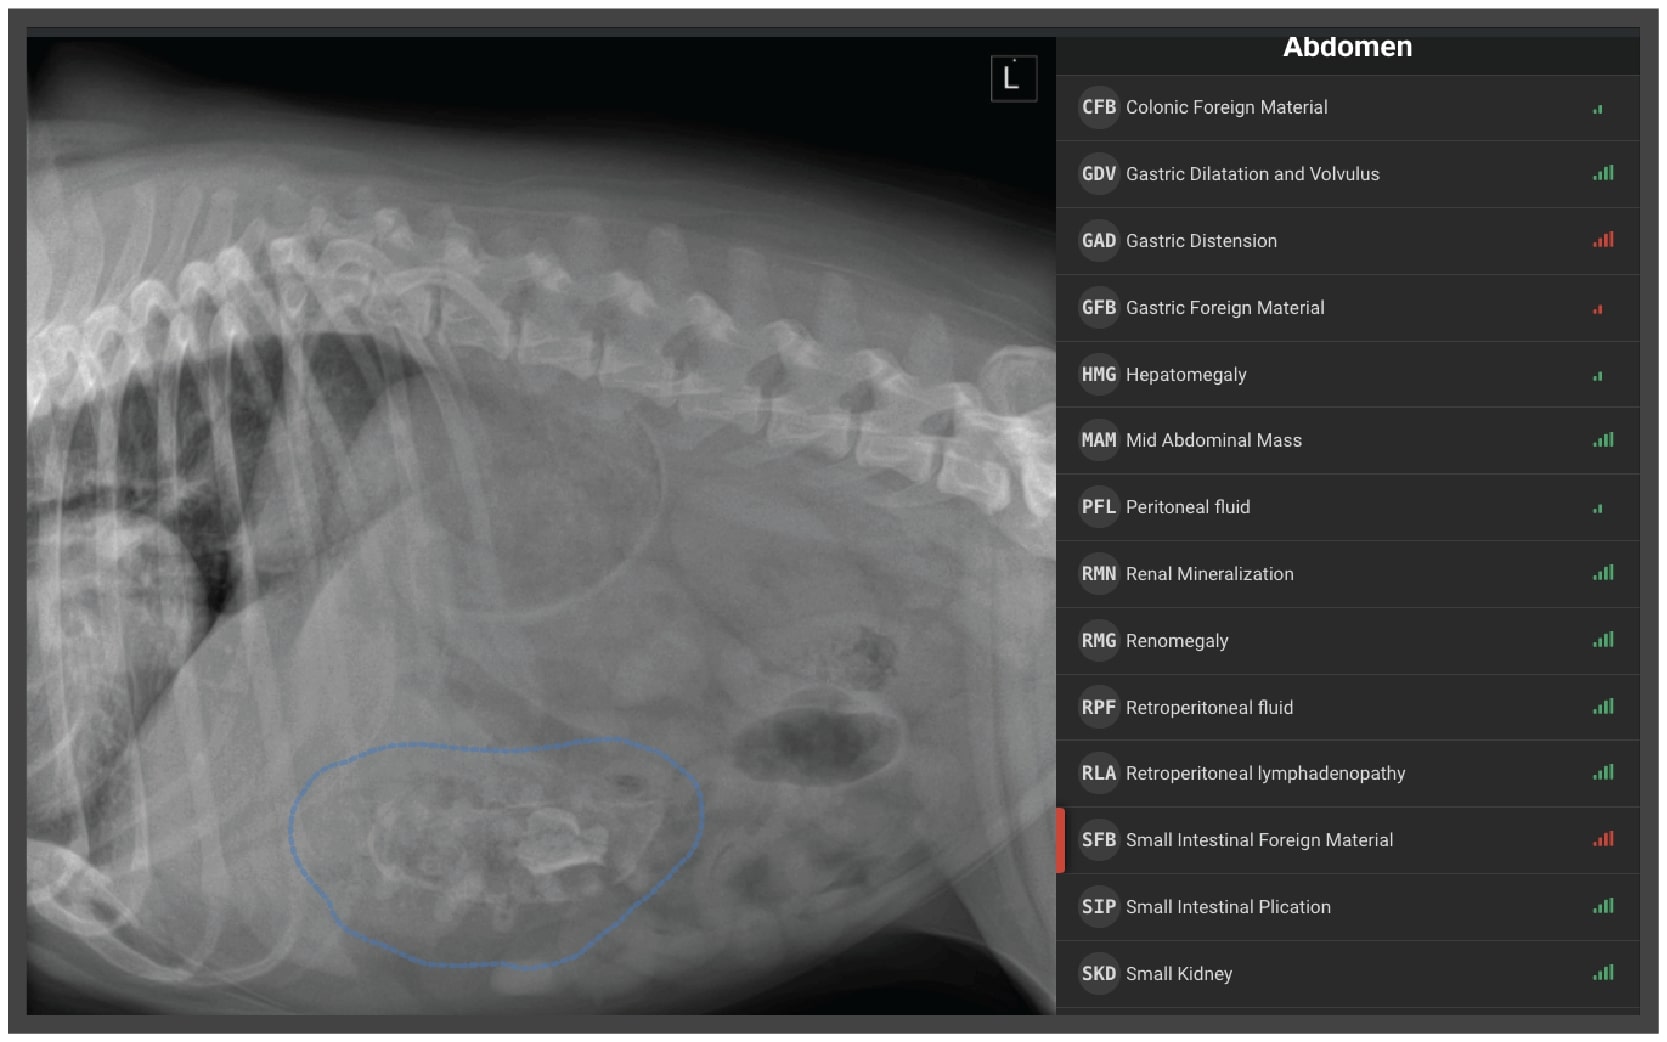

From landing.signalpet.com

Radiology Case of the Week Canine Gastrointestinal Foreign Body What Are Gastrointestinal Problems In Dogs Whether it’s mild stomach upset or something more serious, we’ll help you understand the symptoms, causes, and treatments for digestive problems in dogs. It is important to learn about what could make your dog sick, so you can. Gastrointestinal (gi) disorders and diseases affect a dog's stomach and intestines, resulting in pain and other problems. Diseases that affect the stomach. What Are Gastrointestinal Problems In Dogs.

Radiology Case of the Week Canine Gastrointestinal Foreign Body What Are Gastrointestinal Problems In Dogs Here are seven digestive problems in dogs you should be aware of. Your complete, accurate description of your dog’s history (age, signs of illness, current diet, past problems, exposure to other dogs, and so on). Whether it’s mild stomach upset or something more serious, we’ll help you understand the symptoms, causes, and treatments for digestive problems in dogs. Gastroenteritis is. What Are Gastrointestinal Problems In Dogs.